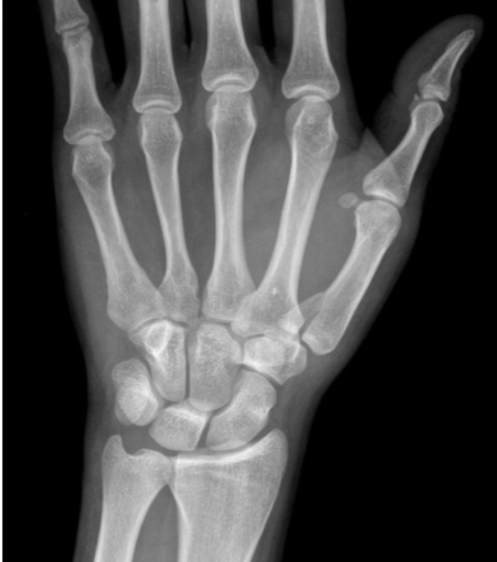

Fratura de Chaffeur

Fratura do processo estilóide do rádio.

Fratura de Bennett

Fratura da base do primeiro metacarpo;

Intra-articular;

Dois fragmentos.